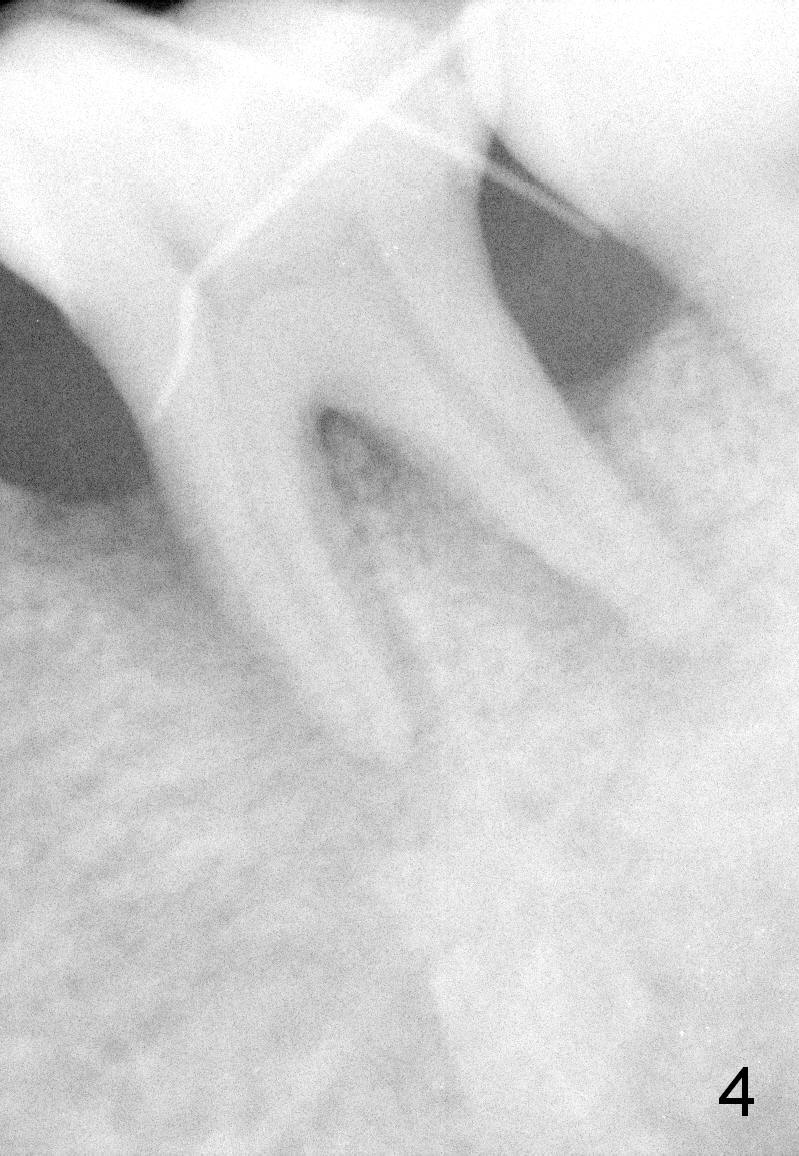

A 43-year-old lady has generalized moderate localized advanced chronic periodontits (Fig.1,2). In spite of 4 quadrant scaling & root planing, the tooth #19 develops 2 perio abscesses (Fig.4 with insertion of 2 guttae perchae); periodontal ligament spaces increases (compare Fig.2,4). It appears that the tooth is non salvageable and should be replaced with an immediate implant (Fig.5). The extraction socket will be treated with Metronidazole. A 2 mm pilot drill is used to start osteotomy in the septum (14 mm deep), followed by reamers until 3.5 mm. A 5x17 mm tap is placed to test stability. If the stability is high, place a 5.3x12 mm SM implant. If insertion torque is too high, use the corresponding drill before re-place the implant. Collagen dressing is placed in the peripheral and deep portion of the sockets, while bone graft in the top portion of the sockets (near implant threads). Use 1 or 2 amalgam carriers to deliver the graft lateral to the implant precisely so that a cover screw does not have to be placed. Next place a cemented abutment. If trajectory of the implant is correct, an abutment as large as 7.8x5(3) mm could be used (pink). Fabricate an immediate provisional. Do not over trim the margin of the provisional so that it can cover the socket completely.